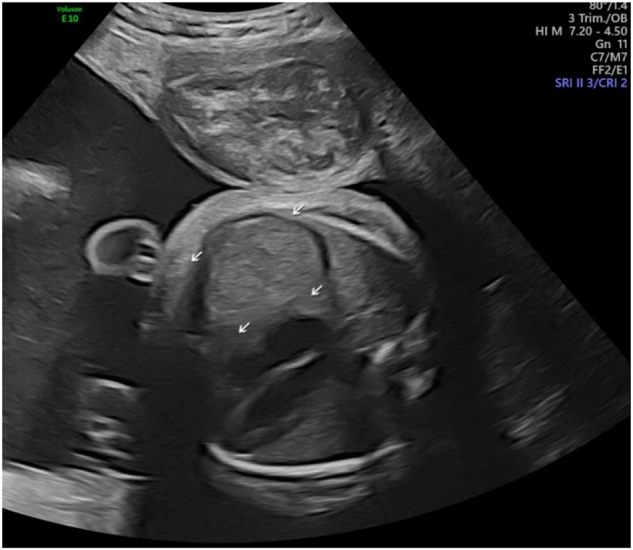

Case presentation: It is the case of prenatally diagnosed cDM. In 32 weeks of pregnancy multiple sonographic findings such as severe polyhydramnios, bilateral talipes, fetal legs akinesia, macrocephaly with mild bilateral ventriculomegaly, right-sided pleural effusion and diaphragmatic pathology were observed by fetal medicine specialist. As the patient complained of weakness in her limbs, she was consulted by a neurologist. The neurological examination revealed a pathognomonic sign of DM1 - grip myotonia. The amniotic fluid and the mother's blood sample were further tested for DM1. This identified >150 repeats in one copy of the DMPK gene of the both, which is consistent with the diagnosis DM1.